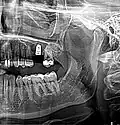

Zahnimplantat Regio 26 unmittelbar nach Implantation und simultanem externem Sinuslift